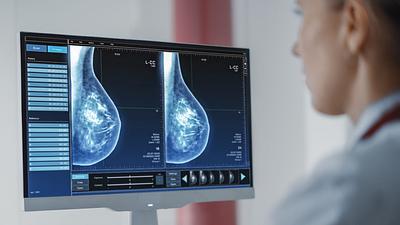

Pesquisa em larga escala aplica IA para detectar câncer de mama

A ferramenta de IA foi aplicada em tempo real e envolvendo um grupo ampliado de pessoas, em vez de ser utilizada posteriormente como vinha sendo feito até agora.